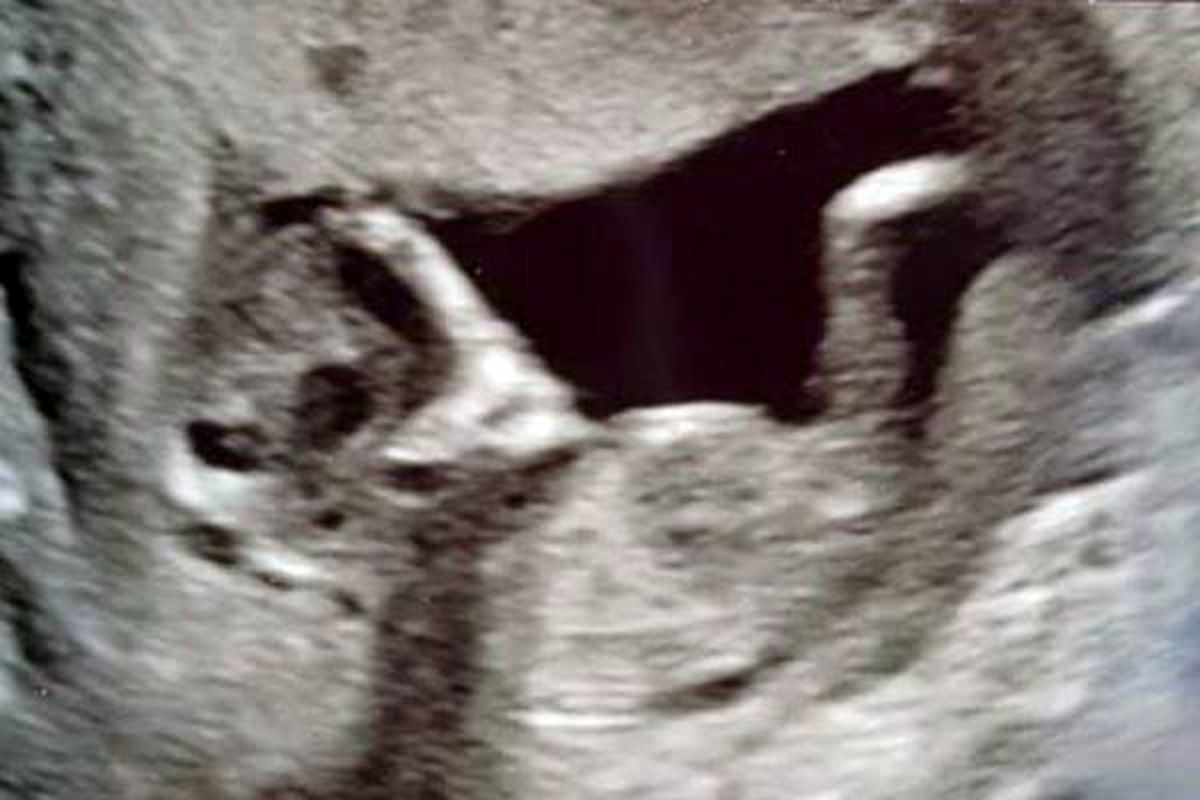

ماجرا از آن قرار است که مادری جوان در انگلیس در سونوگرافی اخیرش با صحنهای عجیب و ترسناک در رحمش مواجه شد که تصمیم گرفت آن را در فضای مجازی انتشار دهد.

سوفی اسکات ۱۶ ساله و استیفن ۲۴ ساله زمانی که برای سونوگرافی به پیش پزشک رفتند با صحنهای عجیب در شکم سوفی مواجه شدند که آنها را تاحدودی ترساند.

در شکم سوفی دو چشم عجیب و ترسناک جنین به چشم میخورد که به شدت به موجودات فضایی شباهت دارد به همین منظور موجب ترس و وحشت آنها شده است.

به گفته سوفی: من ترسیدم که این موجود بیگانه جنین من را خورده باشد و این چشمان چشمهای یک موجود فضایی به جای دخترم در شکمم باشد.